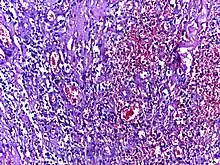

![]() | Tumor giant cell | Malignant neoplasm showing marked anaplasia. Note the marked nuclear pleomorphism, bizarre cells and tumor giant cells. | Category: Histopathology of giant cell tumors | Giant cell tumor |